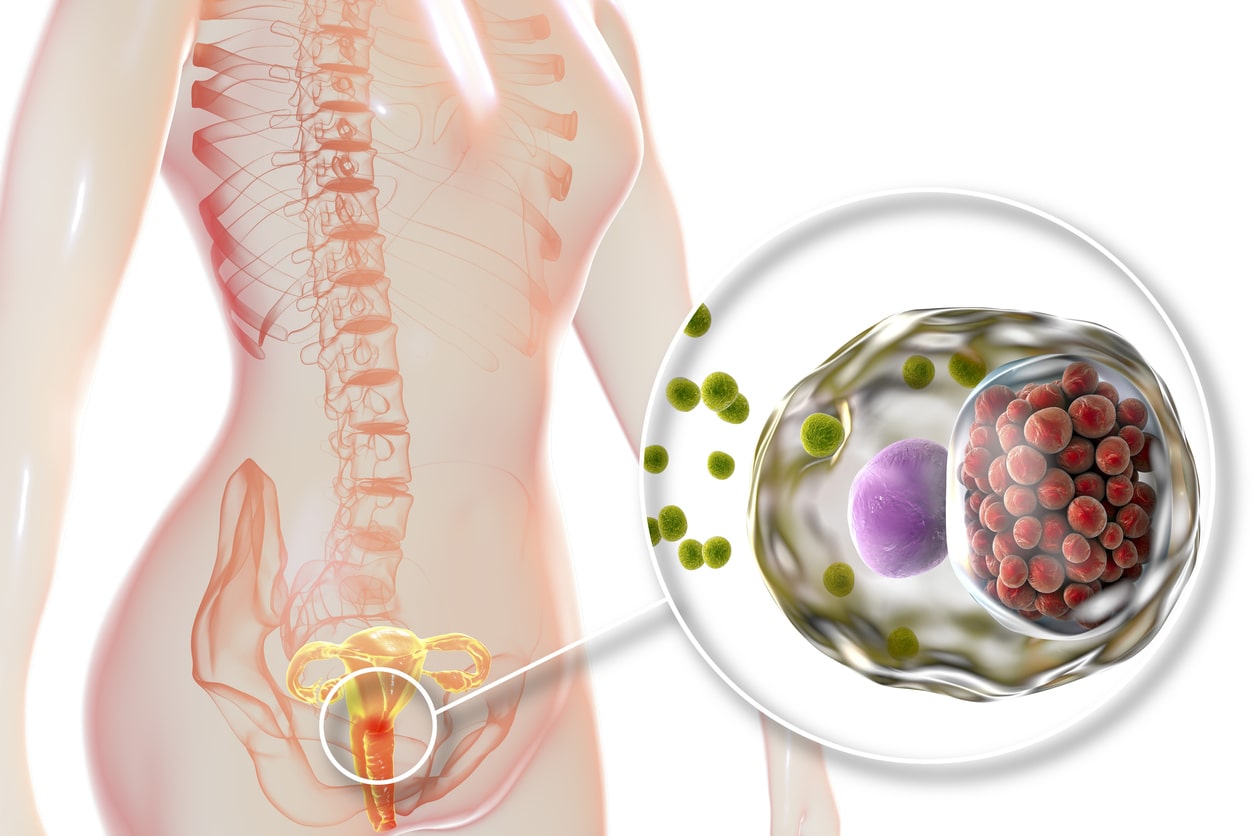

Inilah Gejala-Gejala Sipilis Pada Wanita | by Oval Dwiputra | Medium

Inilah Gejala-Gejala Sipilis Pada Wanita | by Oval Dwiputra | Medium

3 Bakteri Berbahaya Penyebab Penyakit Kelamin di Vagina Anda • Hello Sehat

3 Bakteri Berbahaya Penyebab Penyakit Kelamin di Vagina Anda • Hello Sehat

5 gambar penyakit gonore pada wanita paling nyata

5 gambar penyakit gonore pada wanita paling nyata

3 Bakteri Berbahaya Penyebab Penyakit Kelamin di Vagina Anda • Hello Sehat

3 Bakteri Berbahaya Penyebab Penyakit Kelamin di Vagina Anda • Hello Sehat

3 Bakteri Berbahaya Penyebab Penyakit pada Vagina | HonestDocs

3 Bakteri Berbahaya Penyebab Penyakit pada Vagina | HonestDocs